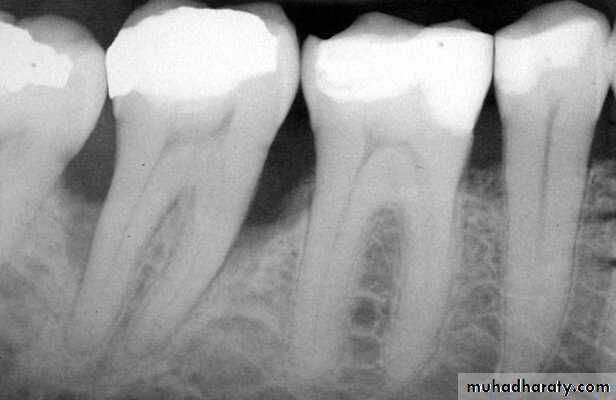

Another point concerns a frequent mistake in “reading” periapical radiographs.

Roots containing two canals are often hourglass shaped. When an X-ray beam passes directly through this structure (center image), the buccal and lingual portions of theroot are in the same path (arrows). These will change with distal and mesial projection. Because a double thickness of tooth structure is penetrated by the X-rays, it is seen in

the film as a radiopaque root outline in close contact with the lamina dura .

By aiming the cone 20° from the mesial, however, the central beam passes through the hourglass-shaped root at an angle (Figure 9A-14). In this case, the two thicknesses of the root are projected separately onto the film. Because less tooth structure is penetrated by the X-ray, the image on the film is less dense. A radiolucent line is clearly seen (open arrow). This radiolucent line can be erroneously interpreted as a canal. By following up the length of the line, instead of entering the pulp chamber, the line can be traced to the gingival surface of the root; this is the PDL space. This simple interpretive error can easily lead to gross mistakes.